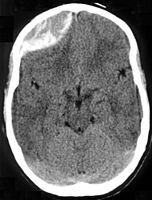

Diagnosis is typically by CT scan or MRI.[1] MRIs have greater sensitivity and should be used if there is a high suspicion of epidural hematoma and a negative CT scan.[3] Differential diagnoses include a transient ischemic attack, intracranial mass, or brain abscess.[3]

Epidural hematomas usually appear convex in shape because their expansion stops at the skull's sutures, where the dura mater is tightly attached to the skull. Thus, they expand inward toward the brain rather than along the inside of the skull, as occurs in subdural hematomas. Most people also have a skull fracture.[3]

Epidural hematomas may occur in combination with subdural hematomas, or either may occur alone.[10] CT scans reveal subdural or epidural hematomas in 20% of unconscious people.[15] In the hallmark of epidural hematoma, people may regain consciousness and appear completely normal during what is called a lucid interval, only to descend suddenly and rapidly into unconsciousness later. This lucid interval, which depends on the extent of the injury, is a key to diagnosing an epidural hematoma.[3]